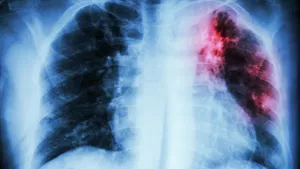

První kazuistika se týká úmrtí mladého muže s nemalobuněčným karcinomem plic metastazujícím do mozku. Soudní znalec byl osloven s tím, že péče o tohoto pacienta byla zanedbána – rodina si stěžovala na fakt, že onkologické onemocnění nebylo diagnostikováno při prvním pobytu ve zdravotnickém zařízení, kde byl nemocný vyšetřován pro rozpadovou dutinu v horním plicním laloku, v tu dobu měl akutní potíže. Byla mu nasazena antibiotika, po kterých došlo ke zmírnění obtíží, takže byl případ uzavřen jako pneumonie s rozpadem, a muž byl s léčbou odeslán do domácí péče. Doporučeno bylo CT vyšetření plic. To následně prokázalo tumor plic, který byl adekvátně diagnostikován a léčen, avšak neúspěšně.